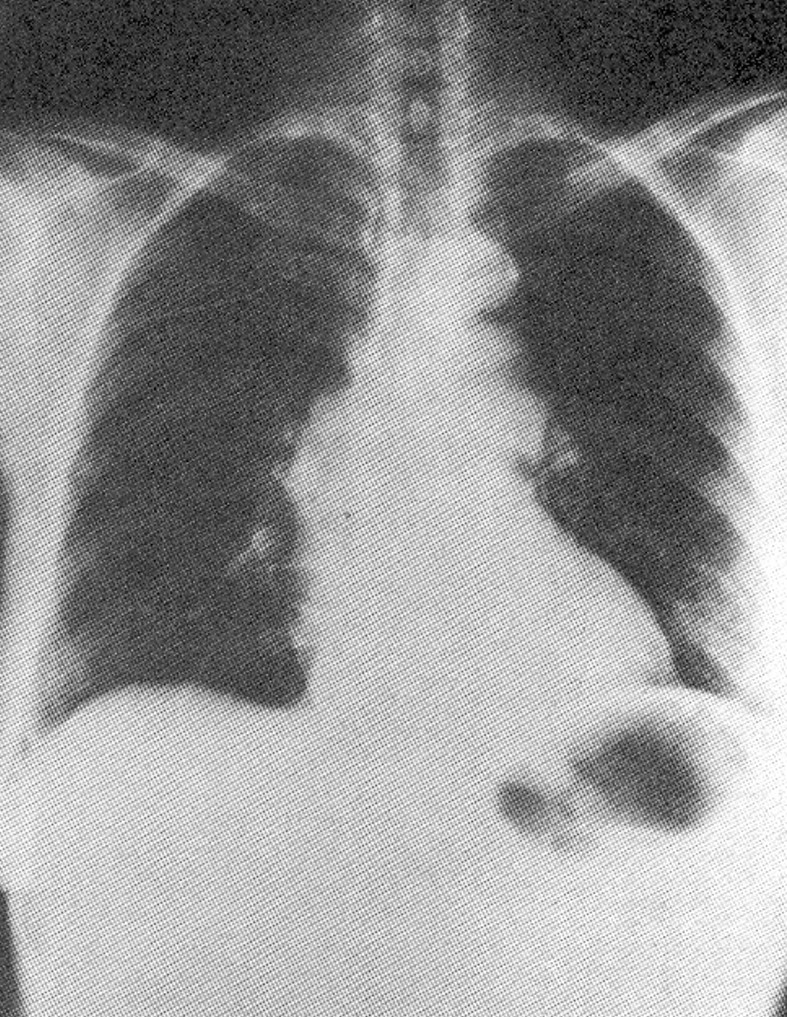

BONUS QUESTION ANSWER: Coarctation of the aorta. The chest x-ray shows a classic "3" sign in the aorta

(the aortic arch, the constriction, and the post-stenotic dilation).